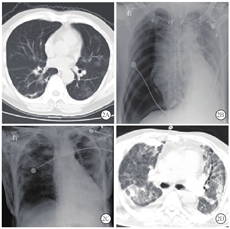

新冠肺炎患者胸部CT表现为:①早期:病变局限,呈斑片状、节段性磨玻璃影,多伴有小叶间隔增厚;②进展期:病灶增多、范围扩大,可累及多个肺叶,部分病灶实变,磨玻璃影与实变影或条索影共存;③重症期:双肺呈弥漫性病变,以实变影为主,合并磨玻璃影,多伴条索影,支气管充气征[1]。本组患者胸部CT显示病灶进展均较快,1例在1周内从早期演变为进展期,2周内演变为重症期,4周后并发气胸,2周后气胸吸收(图1);其余6例患者入院时胸部CT即表现为进展期,均在1~2周内进展为重症期,多表现为双肺弥漫性实变影、条索影及纤维化,胸膜粘连明显,病灶吸收极缓慢(图2)。由于患者病情进展快,病情危重时难以行胸部CT检查,导致影像学资料不齐全。

新冠肺炎患者并发气胸时较隐匿,症状不典型,且患者大多处于镇静状态,极易漏诊。1例未行气管插管的患者因剧烈咳嗽后突发心悸、胸闷,行床边胸部影像学检查提示右侧气胸(肺组织压缩20%)。6例行气管插管机械通气治疗的危重型患者气道压均控制在30 cmH2O(1 cmH2O=0.098 kPa)内。发生气胸前,2例患者镇静程度较浅,出现烦躁不安,人机对抗明显;其余4例处于镇静状态,发生气胸时并无明显诱因。发生气胸后患者病情突然变化,血氧饱和度进行性下降,自主呼吸与机械呼吸不合拍,潮气量下降至200 mL以下,难以升至300 mL,呼吸频率加快,随后患侧逐渐出现头颈部及胸壁皮下气肿,触诊有捻发感,叩诊呈鼓音,其中3例患者很快出现心率减慢,血压下降。气管插管后发生气胸时间在3 d内5例,11 d后发生有1例(表1)。

本组患者病情危重,难以外出进行胸部CT检查,且新冠肺炎为传染性疾病,病区较多且分散,难以做到每个病区配备床边数字化X线摄影(DR)机,故6例患者中仅2例及时行胸部X线检查,提示大量气胸1例;1例行床旁肺部超声检查,提示右侧胸腔无胸膜滑动征,M超下呈条码征,未找到"P"点,考虑诊断为大量气胸;其余3例借助5 mL注射器诊断性穿刺帮助诊断(表2)。